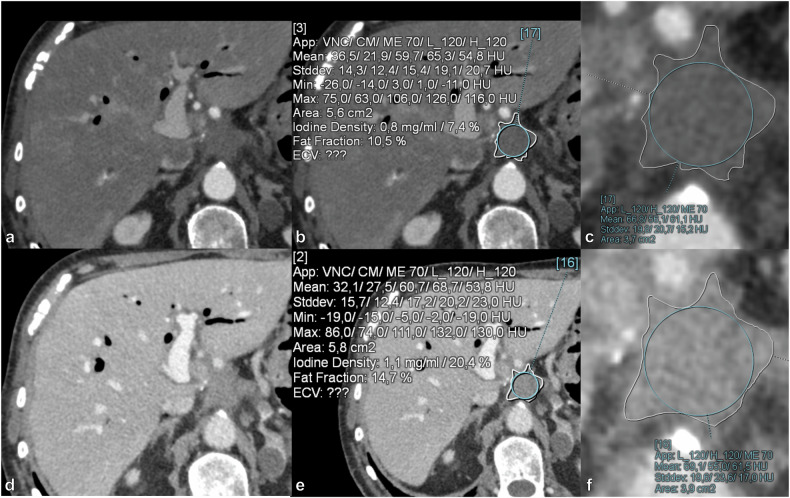

Methods: Seventy-three consecutive PCD-CT scans in 73 patients with postoperative soft-tissue lesions (PSLs) were included, 42 with POC and 31 with LTR. Regions of interest were drawn in each PSL, and spectral variables were calculated: iodine concentration (IC), normalized IC (NIC), fat fraction, attenuation at 40, 70, and 90 keV, and slope of the spectral curve between 40-90 keV. Multivariable binary logistic regression models were constructed. Diagnostic performance was assessed for LAP and PVP using receiver operating characteristic analysis.

Results: In LAP, all variables except fat fraction showed significant differences between LTR and POC (p ≤ 0.025). In PVP, all variables except NIC and fat fraction demonstrated significant differences between LTR and POC (p ≤ 0.005). Logistic regression analysis included NIC and 70 keV in the LAP-based model and IC and 90 keV in the PVP-based model. Both models achieved a higher area under the curve (AUC) than individual spectral variables in each phase. The LAP-based model achieved an AUC of 0.919 with 94% sensitivity, 84% specificity, and 87% accuracy, while the PVP-based model reached 0.820, 71%, 88%, and 81%, respectively.

Relevance statement: Measuring normalized iodine concentration and attenuation at 70 keV in late arterial phase, or iodine concentration and attenuation at 90 keV in portal venous phase, and incorporating these values into a logistic regression model can help differentiate between local tumor recurrence and postoperative changes after pancreatic ductal adenocarcinoma resection.

Key points: Distinguishing recurrence from postoperative changes on CT after pancreatic ductal adenocarcinoma resection is challenging. PCD-CT spectral variable values differed significantly between local tumor recurrence (LTR) and postoperative changes (POC). Logistic regression of spectral variables can help distinguish LTR from POC. The late arterial phase-based model reached an AUC of 0.919 with 94% sensitivity and 84% specificity.